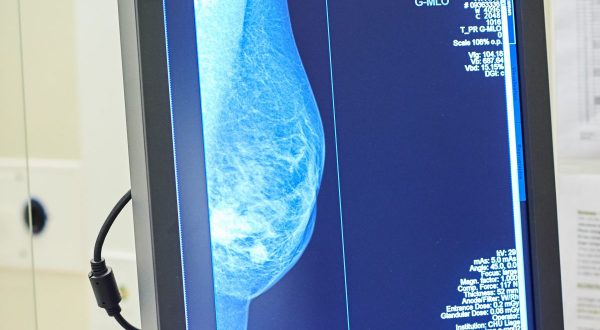

Tumore al seno, Europa Donna “Test genomici non ancora rimborsati”

ROMA (ITALPRESS) – A quasi tre mesi dall’istituzione dell’apposito fondo nazionale di 20 milioni di euro, i test genomici per il carcinoma mammario non sono ancora disponibili gratuitamente in tutta Italia. “Per migliorare la qualità di vita delle pazienti e permettere risparmi di preziose risorse pubbliche bisogna accelerare le procedure affinchè questi esami siano disponibili senza alcuna spesa. Per questo chiediamo un intervento diretto e immediato del Ministero della Salute affinchè approvi al più presto il decreto attuativo”. E’ questo l’appello che sostiene Europa Donna Italia, il movimento per la tutela dei diritti delle donne con tumore al seno che a inizio 2021 ha avviato la campagna nazionale “Chemio: Se Posso la Evito”. I principali risultati dell’iniziativa sono stati presentati oggi in una conferenza stampa virtuale. In poco più di due mesi sono state raccolte oltre 15.000 firme ad una petizione on line. Sono poi stati raggiunti oltre 564mila utenti del web attraverso un’intensa attività sui principali social media.